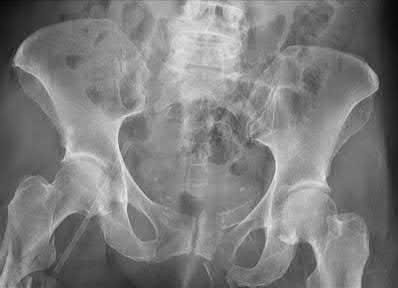

A 35 year-old female presents after prolonged extrication from a motor vehicle collision complaining of severe pelvic pain. Physical examination reveals diminished perianal sensation. She is otherwise neurologically intact. Figures A through D are radiographs and representative CT cuts of her injury. Which of the following nerve roots has likely been injured by the acute trauma?

The clinical scenario is consistent with a high-energy sacral fracture. The radiographs in figures A and B demonstrate a sacral fracture with posterior displacement of the right hemipelvis seen on the inlet view. Figures C and D are axial and sagittal CT images which show a displaced fracture of the right

hemisacrum along with a transvere fracture component through the S3 body . Diminished perianal sensation is concerning for an S2 nerve root injury.

Mehta et al reviewed the current management of sacral fractures. They note that the S1 and S2 nerve roots are more likely to be injured with sacral fractures as they occupy 1/3 to 1/4 of the neural foramina, as opposed to S3 and S4, which only occupy 1/6 of the neural foramina.

Robles reviewed the current literature to ascertain principles of evaluation and treatment for transverse sacral fractures. The author notes that injury to nerve roots S2 to S5 is manifested by impairment of urinary and anal continence and sexual function.